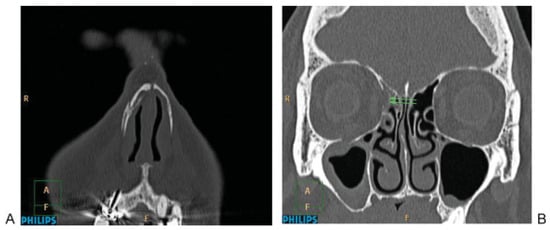

CBCT may adequately evaluate all six mandibular regions defined in the classification system using an adequate examination volume, including the whole mandible. CT should be performed in multidetector CT technique with narrow slice thickness independent of the number of detectors, for example, 16 × 0.75 on a 16-slice CT or 64 × 0.625 on a 64-slice CT scanners. In general, bone and soft tissue windows should be assessed using at least 1 mm axial slices generated for multiplanar evaluation. Multidetector CT technique is increasing in regards to speed and resolution with even more than 256 detectors. 2D multiplanar reconstructions, especially coronal and parasagittal parallel to the ascending ramus are mandatory. 3D CT reconstructions are helpful to identify relevant displacement of fractures and evaluate condylar head displacement and dislocation at the level of the temporomandibular (TMJ) joints.[14] Systematic evaluation of the mandible in CT begins with the evaluation of axial slices to detect direct fracture signs, especially in the symphysis, body, angle/ramus, coronoid, and condylar process, in this order (Figure 1A,B). Coronal reconstructions (Figure 1C,D) or panoramic 2D reformations (Figure 1E) are especially useful for the evaluation of these regions. Bilateral oblique sagittal 2D reconstructions parallel to the ramus/condylar process allow evaluation of the TMJ and its relationship to the glenoid fossa.

Figure 1. Systematic analysis of a mandibular fracture. (A) Axial slice: evaluation of the symphysis/parasymphysis region with a fracture component on the left (arrows). (B) Axial slice: Involvement of the left mandibular body bicortical without displacement (arrows). (C) Twodimensional coronal reconstruction at the symphysis/parasymphysis region (fracture left: arrows). (D) Two-dimensional coronal reconstruction with the fractures at the inner cortical part of the mandibular body left (arrows). (E) Two-dimensional panoramic reconstruction showing the involvement of the left mandibular body, and symphysis.